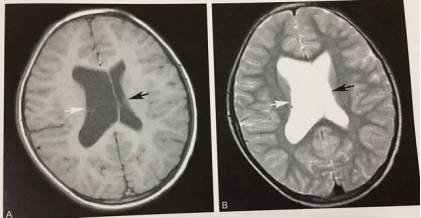

6、双侧侧脑室发育不对称

T1WI及T2WI显示双侧侧脑室发育不对称,右侧侧脑室发育相对较大,左侧侧脑室发育正常,脑组织信号正常。